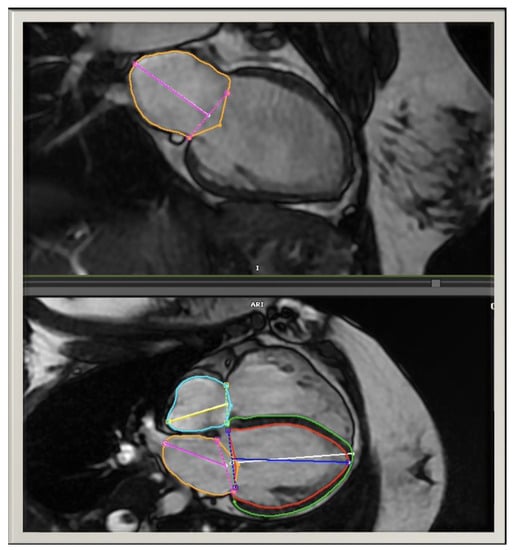

2.3. CMR